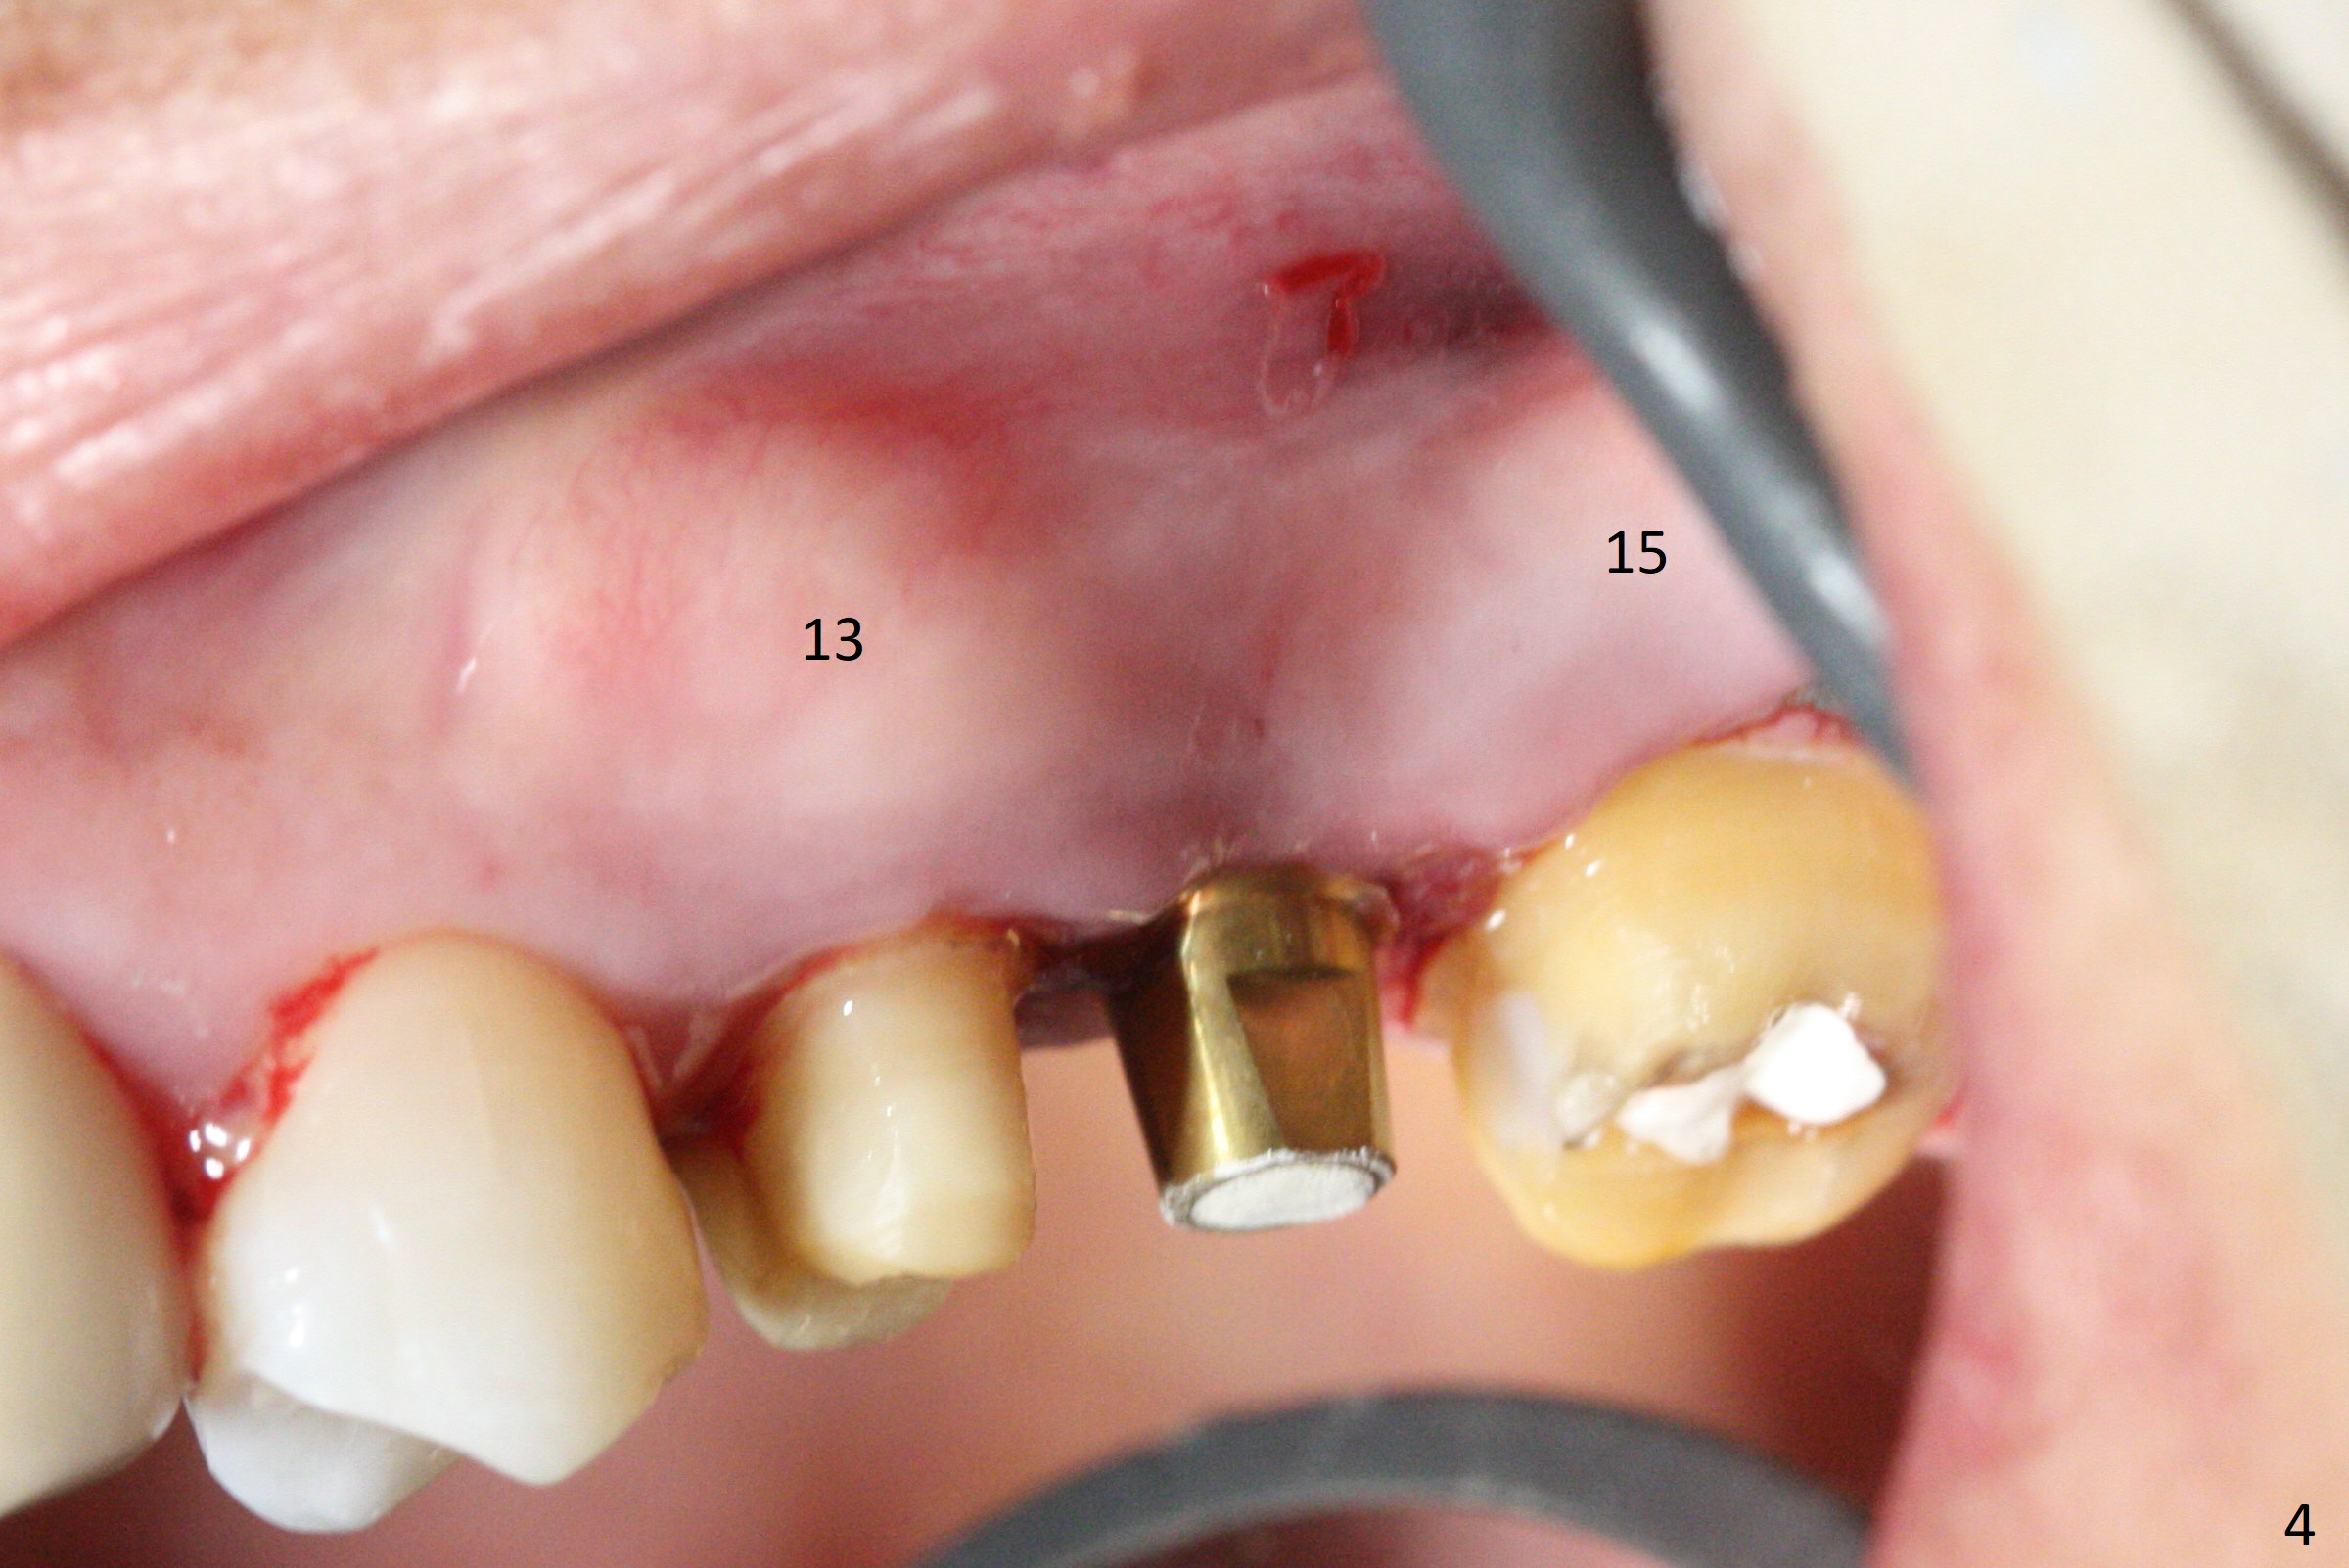

#13-15 FPD has not been used properly because of discomfort for 2 years. Before its removal, the discomfort derives from probing of the distal of #13 and mesial of #15, corresponding to calculus in the proximal areas. SRP is performed in UL quadrant after FPD removal. Bone density at the crest of the edentulous area is normal, while that of the medulla is low. After determination of trajectory and depth of initial osteotomy (Fig.1 (5 mm straight incision)), the site is underprep for a 4.5x13 mm Implant. Following adjustment, the implant is placed slightly subcrestal (Fig.2,3). It is possible that the discomfort of the previous FPD is due to overload, as suggested by the prominent buccal plate at #13 and 15, as compared to that of #12 (Fig.4 (5.2x4.5(3) mm cementation abutment at #14). Postop follow up shows that the tooth #15 may need RCT. The implant seems to enter the sinus (Fig.5 (2.5 months postop)) and be ready for restoration 3.5 months postop (Fig.6).